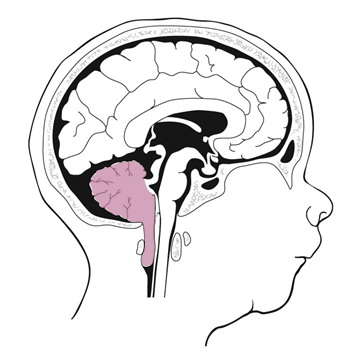

小脑扁桃体下疝合并脊髓空洞症(Chiari畸形)是神经外科的常见疾病,由于脊髓空洞的形成导致了脊髓的损伤,使患者出现肢体感觉运动的功能障碍,严重降低了患者的生活质量,甚至导致患者出现残疾。

小脑扁桃体疝出枕大孔下缘5mm,就可以诊断为小脑扁桃体下疝。

正常情况下在枕大孔区域有良好的脑脊液循环,脑脊液可以在颅腔和椎管自由流动。

在出现小脑扁桃体下疝的时候,小脑扁桃体阻塞了枕大孔区域的脑脊液循环。导致脊髓空洞形成,脊髓空洞破坏了脊髓神经纤维,导致患者出现感觉和运动功能障碍,严重的甚至出现肌肉萎缩。

因此,对这种疾病的治疗关键是解除小脑扁桃体在枕大孔对脊髓的压迫,同时重建枕大孔区域的脑脊液循环。常规的治疗方式是后颅窝减压-枕大池成型术。